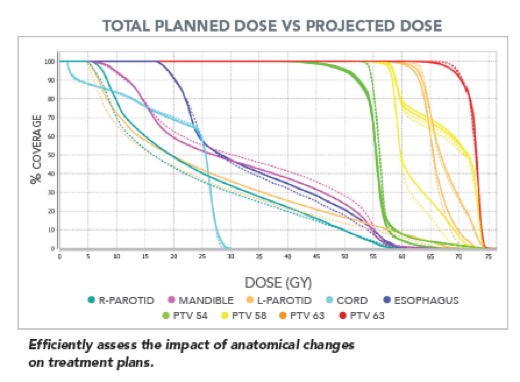

Το σύστημα διαθέτει εργαλεία για την αξιολόγηση των καθημερινά χορηγούμενων κατανομών δόσης επιτρέποντας στους ιατρούς να αναγνωρίσουν πια πλάνα χρειάζονται αναπροσαρμογή.

Το σύστημα διαθέτει εργαλεία για την αξιολόγηση των καθημερινά χορηγούμενων κατανομών δόσης επιτρέποντας στους ιατρούς να αναγνωρίσουν πια πλάνα χρειάζονται αναπροσαρμογή.

- Αξιολόγηση της ευθυγράμμισης του ασθενούς σε θέση θεραπείας.

- Αξιολόγηση των ανατομικών και βιολογικών μεταβολών του ασθενούς κατά τη διάρκεια της ακτινοθεραπευτικής αγωγής

- Αξιολόγηση της καθημερινά χορηγούμενης κατανομής δόσης, της αθροιστικής δόσης μέχρι την συγκεκριμένη συνεδρία καθώς και των δοσιμετρικών διαφορών

- Αξιολόγηση της ανταπόκρισης του ασθενούς στην ακτινοθεραπευτική αγωγή.